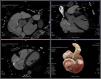

He had undergone no prior aortic surgery nor had he experienced chest trauma. Infections and connective tissue disorders capable of weakening the elastic tissue were excluded. The coronary computed tomography angiography excluded atherosclerotic coronary artery disease and showed the aneurysm again (Figure 2). Postcapillary pulmonary hypertension was confirmed by right heart catheterization and pulmonary–systemic flow ratio (Qp/Qs) was 2.1.